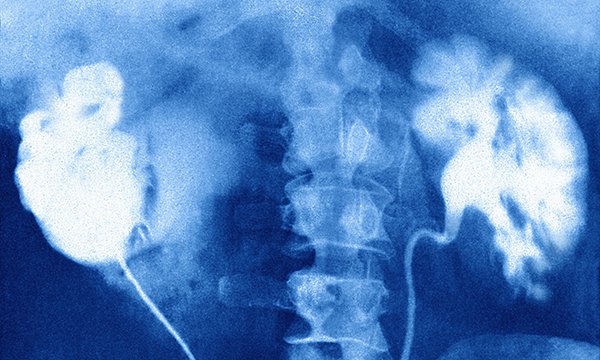

AKI is linked to COVID-19, and the pandemic has affected both its incidence and demographics